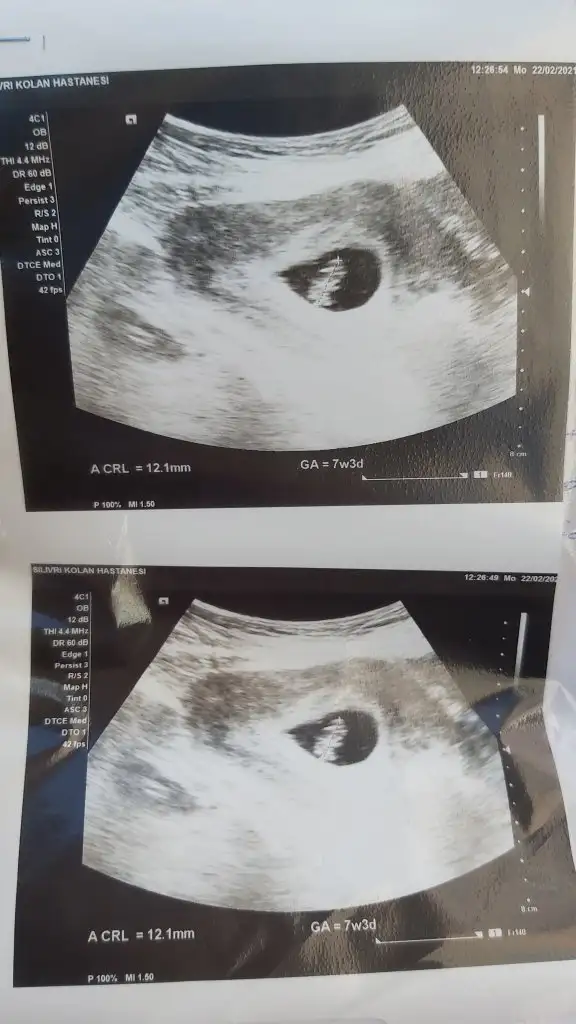

hayırlı olsun canım darısı bize inşAllah :)Kızlar yeni geldim hastaneden kalp atışı duyuldu şükür kese şekline göre cinsiyet tahmini yapıyorlar anlayan var mı kalbi 159 atıyor muş

solda olunca boyle erkek diolardi sanirim.Kızlar yeni geldim hastaneden kalp atışı duyuldu şükür kese şekline göre cinsiyet tahmini yapıyorlar anlayan var mı kalbi 159 atıyor muş

Ben cinsiyet ten anlamıyorum ama maşallah demeye geldimKızlar yeni geldim hastaneden kalp atışı duyuldu şükür kese şekline göre cinsiyet tahmini yapıyorlar anlayan var mı kalbi 159 atıyor muş